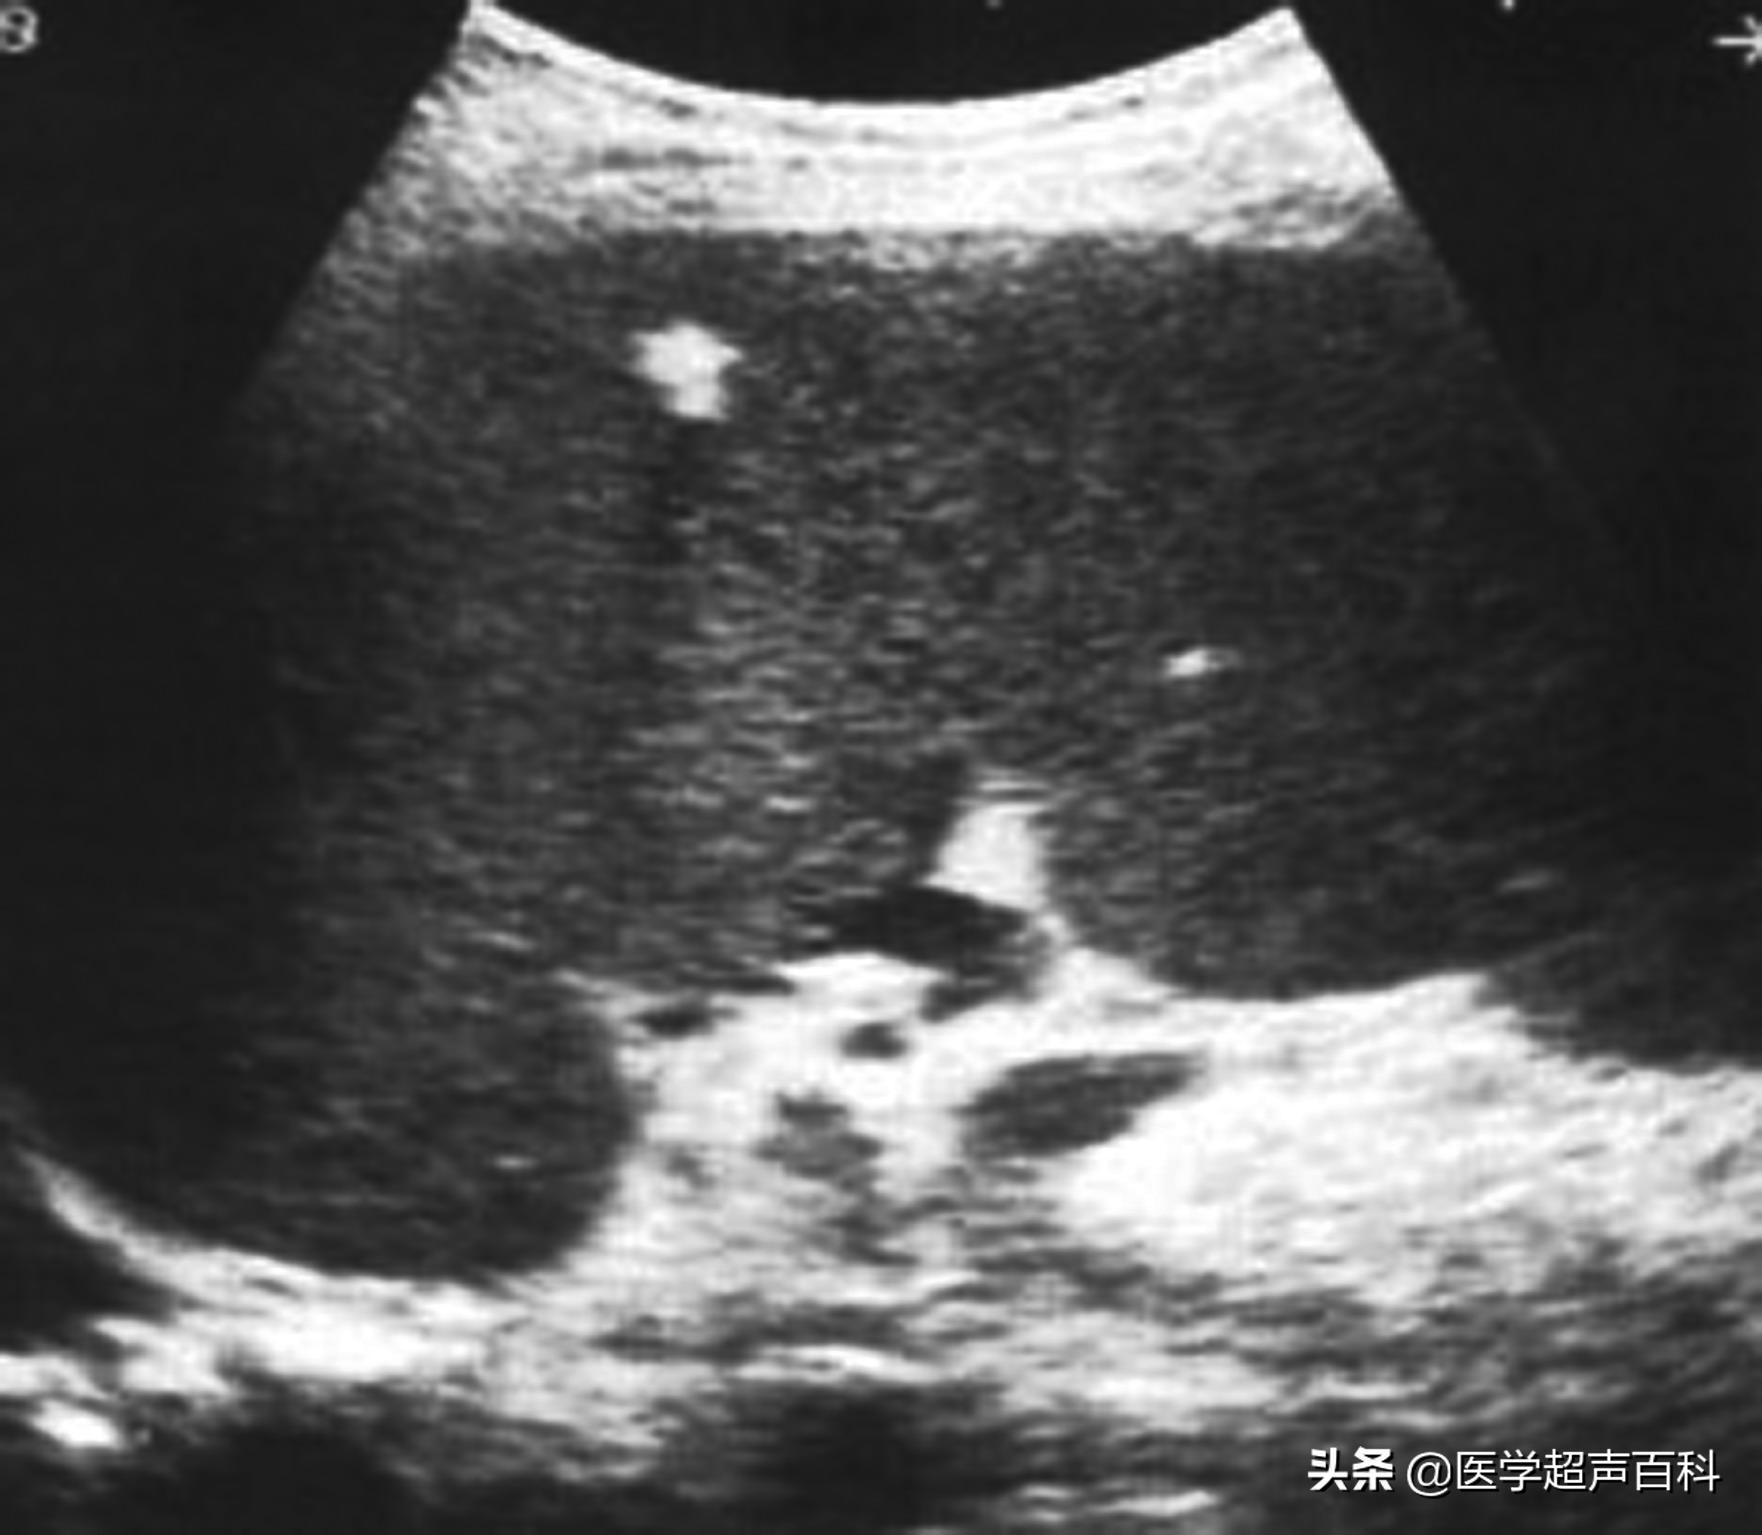

临床上将脾脏肿大分为轻度、中度、高度肿大。肋缘下刚触及至肋下3厘米以内,属于轻度肿大;3厘米至脐水平位置,为中度肿大;超过脐水平,则为高度肿大或称为巨脾。

二、充血性脾脏肿大

因脾脏静脉压力增高,脾脏血液回流受阻、淤血,而导致体积增大。常见于各种原因引起的慢性心功能不全、慢性缩窄性心包炎、各种原因所致的肝硬化及门静脉或脾静脉血栓形成等。充血性脾肿大,常伴腹水。由于红髓内单核巨噬细胞与淋巴细胞增生,小梁增厚,脾索增宽,故充血性脾大易伴有脾功能亢进。